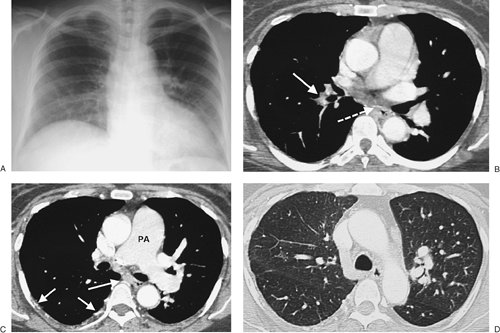

FIGURE 17-5. Acute PE. A: CTPA of a 78-year-old woman shows an intraluminal filling defect surrounded by contrast material in the proximal right lower lobe pulmonary artery (arrow). B: Coronal CTPA shows that the intraluminal filling defect extends from the proximal right lower lobe pulmonary artery inferiorly to distal branches (arrows). C: CTPA with lung windowing shows oligemia and diminution of vessels on the right (Westermark sign).

FIGURE 17-6. Acute PE. A: Posteroanterior (PA) chest radiograph of a 52-year-old woman with cholangiocarcinoma shows a rounded opacity at the left costophrenic angle, representing a Hampton hump of pulmonary infarction. B: CTPA shows a saddle embolus bridging the lingular and left lower lobe pulmonary arteries (arrow). C: CTPA at a more inferior level shows intraluminal filling defects expanding the proximal lower lobe pulmonary arteries (arrows).

FIGURE 17-7. Acute PE. CTPA of a 76-year-old man with acute shortness of breath shows a large intraluminal filling defect within the proximal right lower lobe pulmonary artery (solid arrow) and a smaller intraluminal filling defect within a segmental pulmonary artery to the left lower lobe (dashed arrow).

FIGURE 17-8. Acute PE associated with pulmonary arterial hypertension. A: CTPA of a 23-year-old man involved in a motor vehicle crash shows a saddle embolus straddling the right and left main pulmonary arteries (arrows). The central pulmonary arteries are enlarged. B: CTPA at a more inferior level shows thrombus within segmental branches of the lower lobe pulmonary arteries (arrows). C: CTPA at a level inferior to (B) shows leftward bowing of the interventricular septum (arrow).